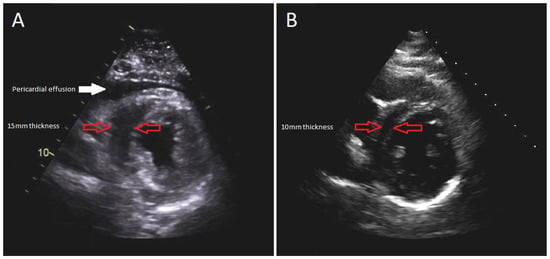

The patient was intubated, and an emergent subxiphoid pericardial window was performed with drainage of 250 milliliters of clear pericardial fluid. The patient’s hemodynamic parameters immediately improved, but not long after the patient became hypotensive and required a large volume of IV fluids totaling 14 L of crystalloid saline. Norepinephrine infusion was also initiated at the rate of 0.1 micrograms/kilograms/minute. The patient’s troponins continued to increase with repeat TTE, demonstrating decreased left ventricular (LV) systolic function to 44% along with moderately increased concentric LV wall thickness (Figure 2A). Despite receiving significant amounts of crystalloid fluid and continuous norepinephrine of 0.15 micrograms/kilograms/minute, she remained in refractory shock, at which time epinephrine was added at the rate of 0.07 micrograms/kilograms/minute.

Figure 2. Parasternal short-axis view of TTE: (A) during the acute illness revealing 15 mm LV wall thickness; (B) 1-month follow-up demonstrating 10 mm LV wall thickness.

Her hospital course was complicated by rhabdomyolysis, acute kidney injury, and intensive care unit-acquired weakness requiring intensive physical therapy. After 20 days of hospitalization, she was discharged to a rehabilitation facility. Her discharge medication regimen consisted of colchicine 0.6 milligrams daily for an anticipated 3-month course and oral furosemide 40 milligrams daily. After one month, a follow-up TTE demonstrated recovered systolic function with LV ejection fraction of 62%, resolution of myocardial edema, and no evidence of recurrent pericardial effusion (Figure 2B). No long-term complications were encountered on a subsequent follow-up.